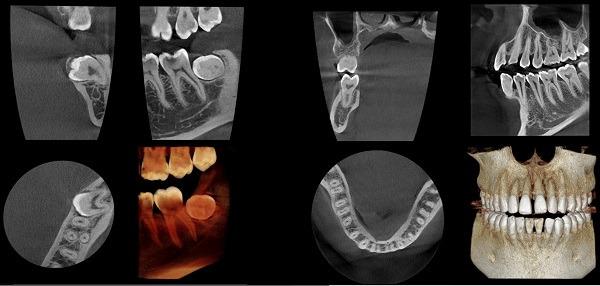

With various scan modes of Panoramic, CT and Cephalometric*, assist in accurate diagnosis.

FOVs of various sizes/resolutions

Minimize the affects of Metal artifact to prevent deterioration of image quality by prosthesis to provide optimal images.

By converting the acquired CT images to STL format, they can be used to

design and manufacture dental prosthetic digital models.